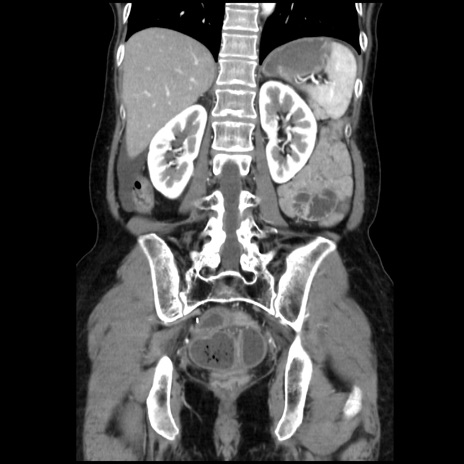

症例32(冠状断像)

【症例】40歳代 女性

【主訴】上腹部痛、嘔気・嘔吐

【現病歴】約9時間前頃から急に上腹部痛、嘔気、嘔吐が出現。改善しないため救急要請。

【既往歴】子宮頚癌(広汎子宮全摘術、放射線療法)、腸閉塞

【身体所見】腹部:平坦、軟、腸雑音亢進、上腹部を中心に腹部全体に圧痛あり。

【データ】WBC 8400、CRP 0.03